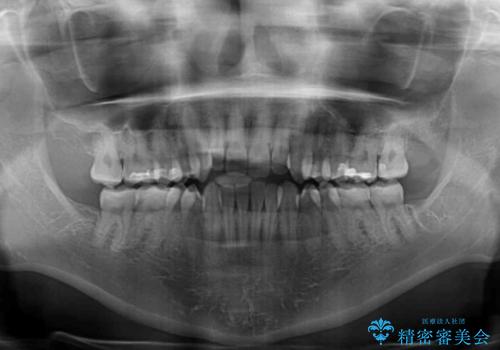

- 前歯の開咬を気にして来院された患者様です。

開咬の治療は、前歯を閉じるように動かすとともに、上下臼歯を圧下(骨内にめり込ませる)させることで進めて行きます。

インビザラインは臼歯の圧下を効果的に行えるため、インビザラインを用いて矯正治療を行うこととしました。